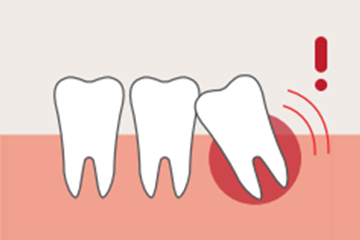

흔히 ‘사랑니’라고 부르는 이 치아의 치의학 명칭은 ‘제3대구치’ 입니다.

세번째로 나는 큰 어금니라는 뜻입니다. 17세~25세 턱뼈의 성장이 완료 된 시점에 새로나는 어금니로 가장 안쪽에 좁은 상태로 나오게 됩니다.

사랑니의 형태는 누워있거나 일부만 보이거나, 혹은 아예 숨어있는 등 여러 형태로, 형태에 따라 발치르 할지 발치 없이 유지관리 할지를 결정하게 됩니다.

많은 치아들 중 턱뼈가 모두 성장한 이후에 가장 늦게 나기 때문에 치열의 가장 안쪽 좁은 곳을 뚫고 나옵니다.

좁은 곳에 나기 때문에 누운 상태로 나거나, 턱뼈를 자극하는 각도로 뿌리를 내리거나, 잇몸에 숨겨진 상태로 나는 등 비정상적으로 자리를 잡게 되기 쉽습니다. 그리고 사랑니는 치열 안쪽 깊숙이 자리해 있기 때문에 칫솔질이 닿기 힘듭니다.